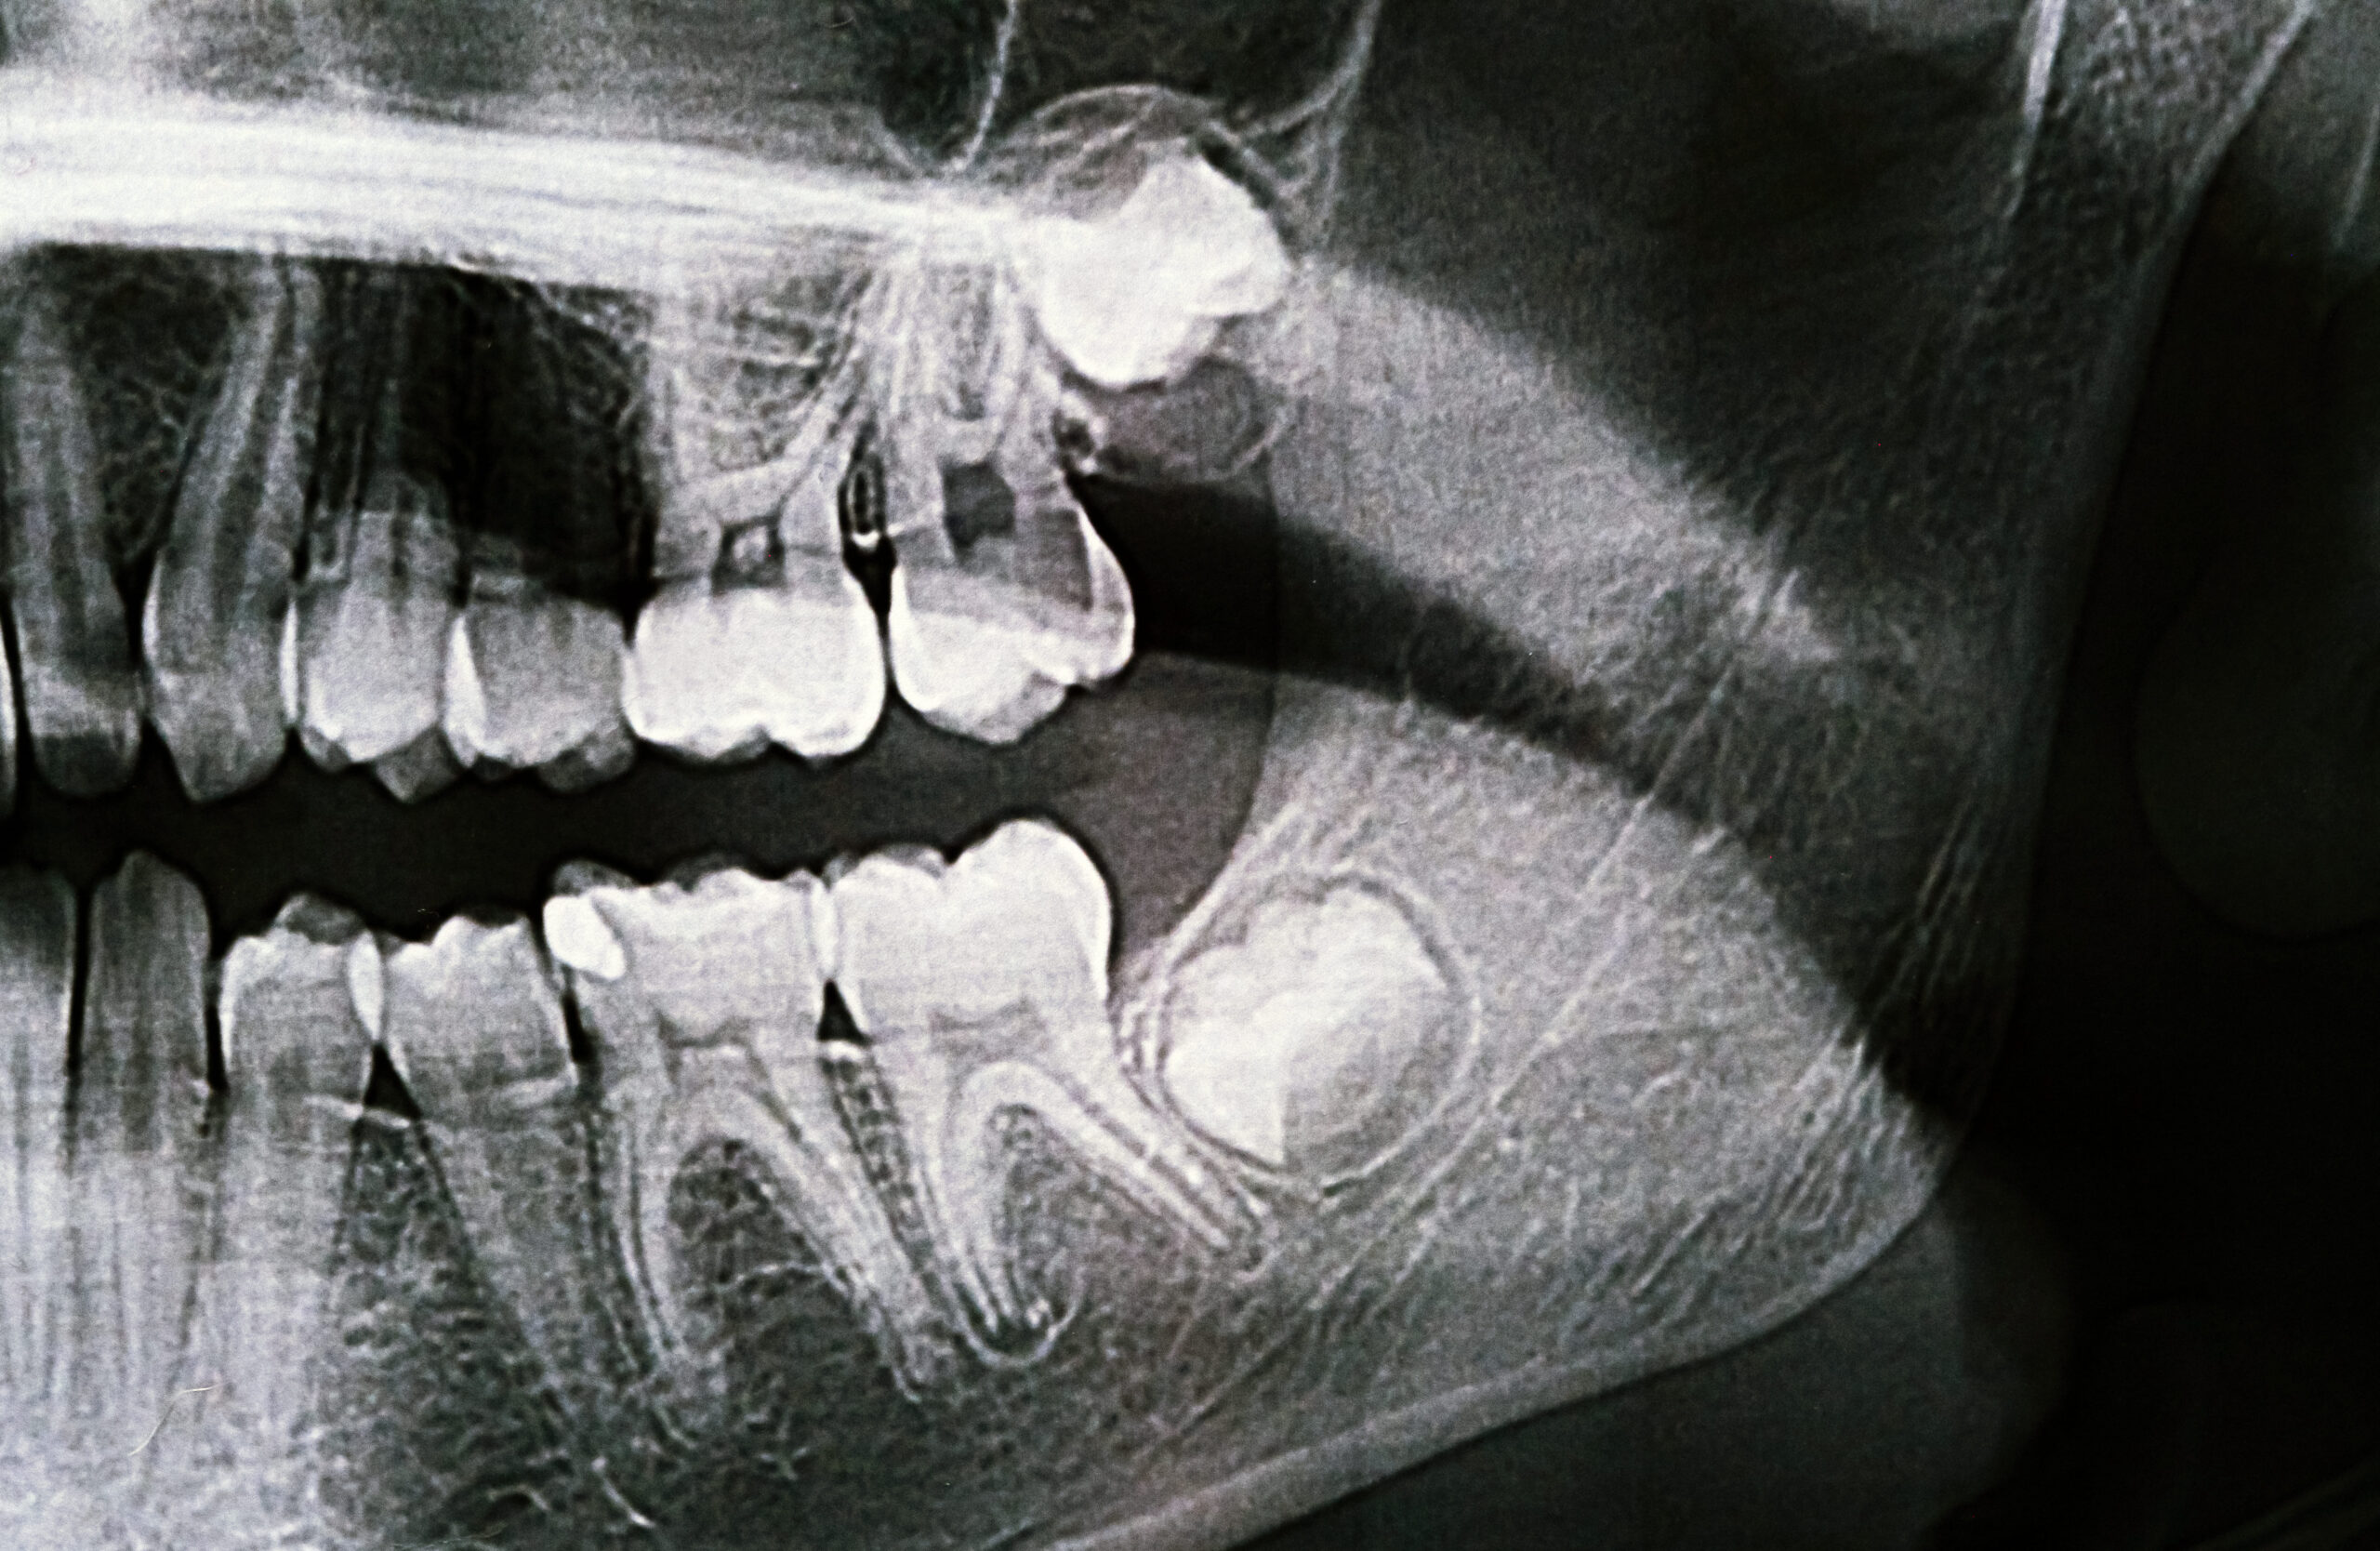

Wisdom Teeth

Wisdom teeth are the last molars to erupt and often lack enough space to grow properly. Impacted wisdom teeth can cause pain, swelling, decay, gum disease, and damage to nearby teeth. Early evaluation and removal help prevent complications and protect long-term oral health.